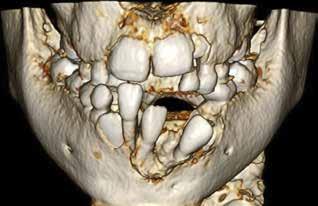

PATIENTTILFÆLDE 1

Patienttilfælde 1 (Fig. 1) er en 37-årig kvinde, henvist efter succesfuld behandling af stadie 3-parodontitis. Der er nu sundt

Før behandling

parodontium, ingen pocher over 4 mm, og både blødnings- og plakindeks er under 10 %. Patienten er motiveret for ortodontisk behandling, da hendes tænder er vandret over tid, delvist som følge af reduceret parodontium.

Der ses anterior trangstilling i begge kæber og overerupterede 1+1 og 2,1-1,2, hvilket resulterer i dybt bid med 2- tæt på ganepåbidning. Der er normale sidetandsrelationer, men der ses 5 mm horisontalt overbid (HOB) og 7 mm vertikalt

overbid (VOB). Papillen mellem 1+1 er betydeligt reduceret pga. fæstetab, og de mesialt kippede 1+1 har resulteret i en ”dark triangle”. Den facioorale funktion er for nuværende i.a. Panoramarøntgen (Fig. 1, I) viser marginalt knogletab i begge kæber og fravær af 8,7+7,8 og 8,7-8.